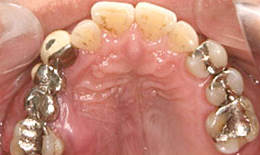

治療前

上顎

保存困難な歯を抜歯後、インプラントを2本埋め込んで、セラミックスクラウンを被せた